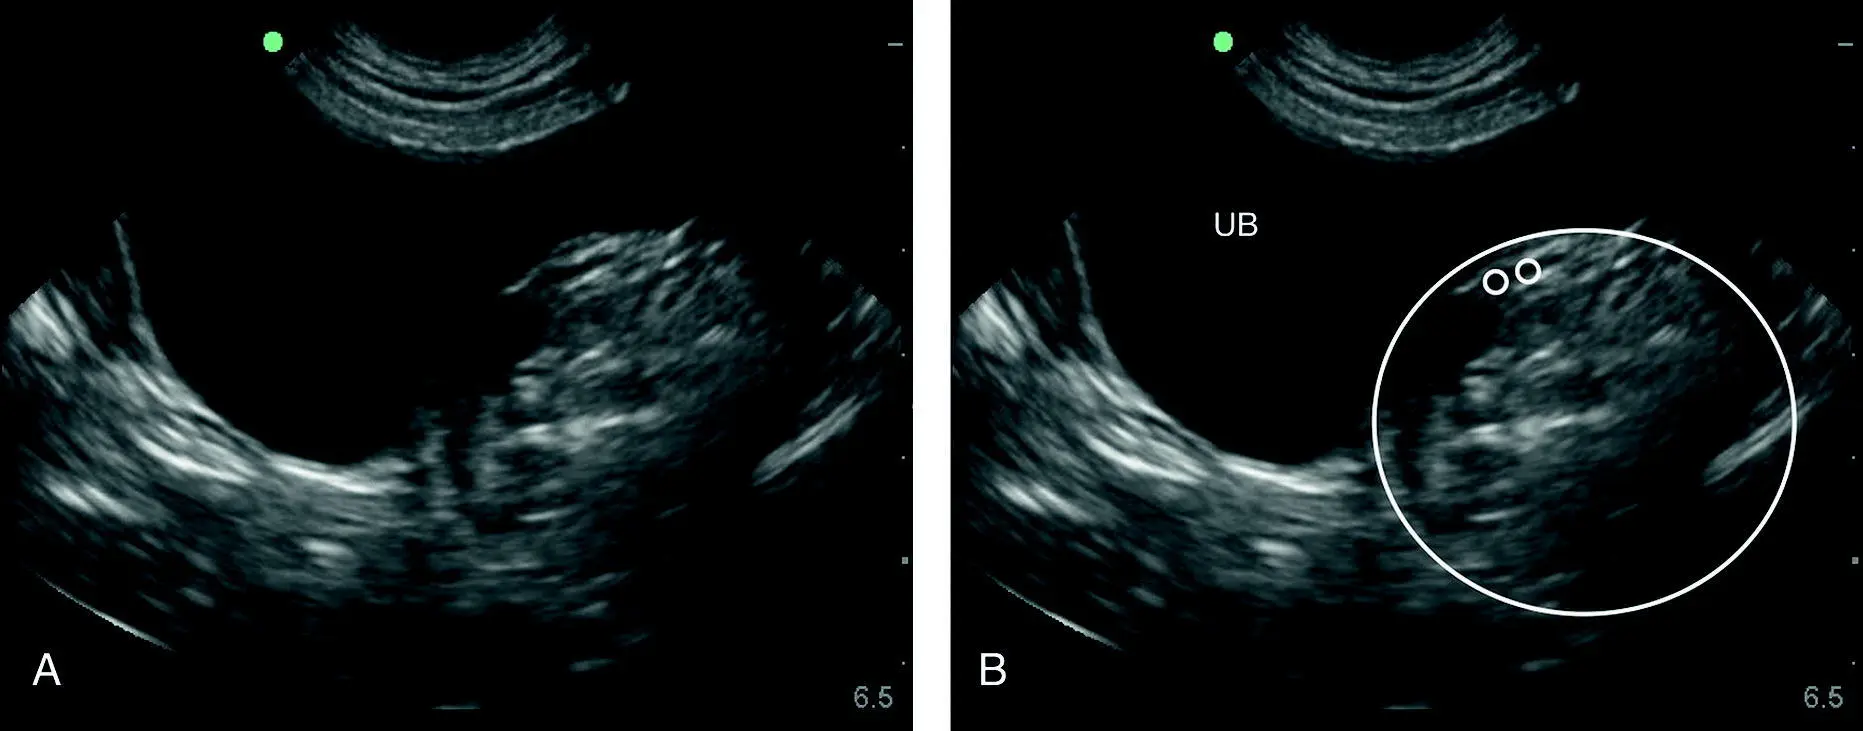

Figure 6.31. Examples of typical negative studies at the HRU (SRU) view. The target organs are the small intestine and spleen. By imaging either or both, the sonographer knows they are within the abdominal cavity. (A) and (B) are the same image labeled and unlabeled, showing how the small intestine in cross‐section, transverse orientation, appears like “hamburgers” and in longitudinal or sagittal appears like “highways.” In (B) the circle highlights an area that may or may not have a small triangulation of free fluid, illustrating the difficulty in seeing small pockets of fluids (milliliters) in between intestinal loops because of the anechoic layers of intestine. A better strategy is shown in (C) by using the spleen as an acoustic window and looking for free fluid on its far side. In (D) is another region in which soft tissue is in proximity to small intestine as a better strategy to detect small‐volume effusions at this view than in (A) and (B).

Source: Reproduced with permission of Dr Gregory Lisciandro, Hill Country Veterinary Specialists and FASTVet.com, Spicewood, TX.